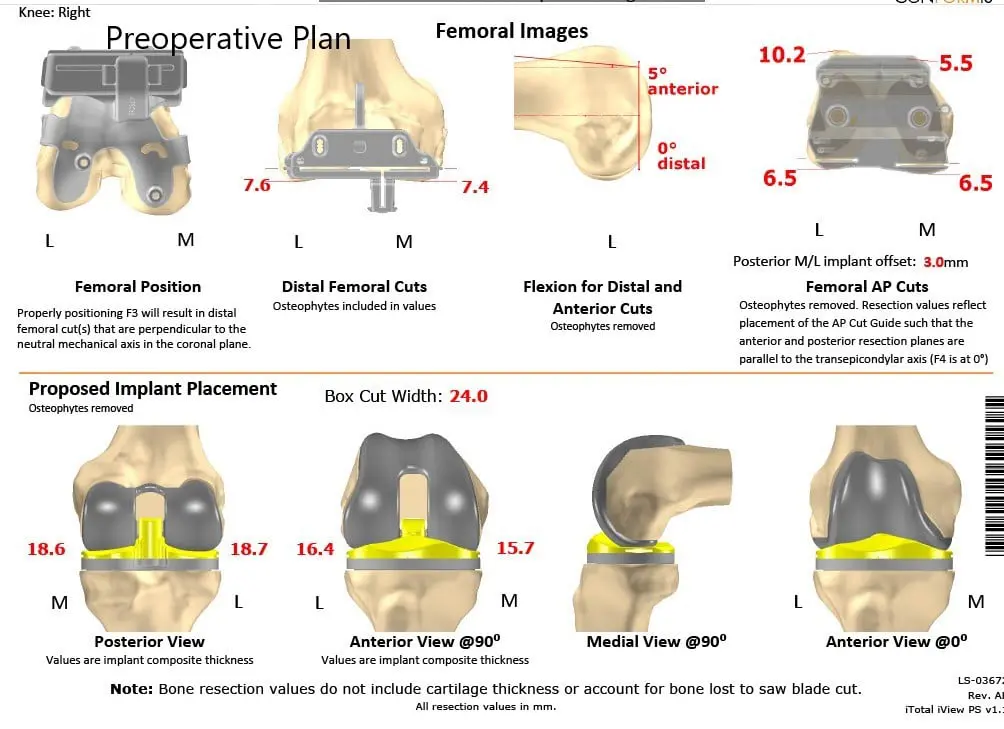

A preoperative CT scan of the right knee including the hip and ankle were obtained a few weeks prior to the surgery. The CT scan images are used to construct a 3D model of the patient’s anatomy. The information from the CT scan was used to create a unique patient-specific implant and instruments.

The instruments which were specific to the patient aided in reducing the amount of bone cut during surgery. The correctly sized patient-specific implant works in unison with the soft tissues of the knee resulting in a more natural feeling knee. The custom knee reduces the need to compromise soft tissues to work with an implant as in the case of off the shelf implants.

Complete Orthopedics patient-specific surgical plan for a custom unilateral knee replacement in a 74-year-old female (scan 2)